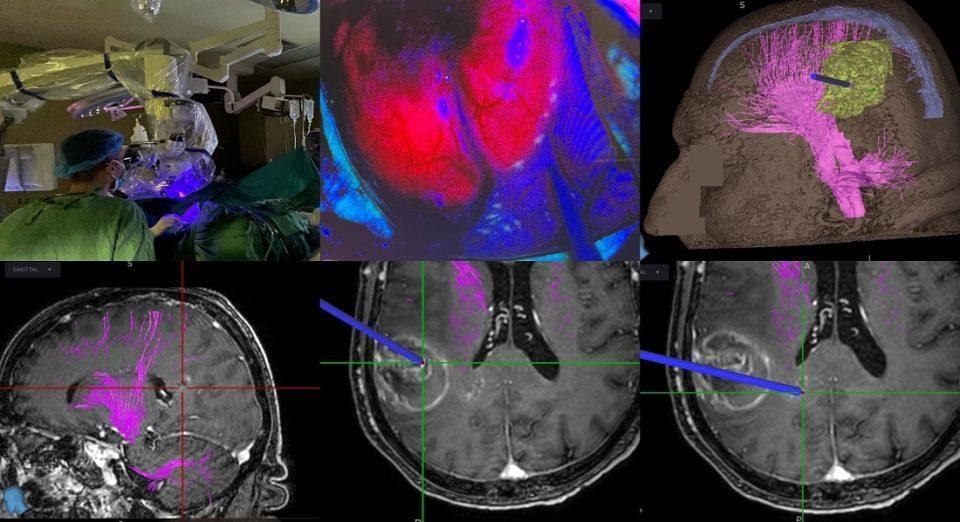

Η χρήση του 5-αμινολεβουλινικού οξέος επιτρέπει τον φθορισμό και αναγνώριση του όγκου διεγχειρητικά με τη χρήση ειδικού τύπου μικροσκοπίου, που διαθέτει η Νευροχειρουργική Κλινική. Έτσι, μπορεί να γίνει αναγνώριση και πιο εκτεταμένη εξαίρεση του νεοπλασματικού ιστού, κάτι που έχει αποδειχθεί ότι αυξάνει την επιβίωση σε ασθενείς με υψηλής κακοήθειας γλοιώματα εγκεφάλου.

Επιπλέον, έγινε διεγχειρητική χρήση νευροπλοηγού, που διέθετε αλγόριθμο νέας τεχνολογίας για δεσμιδογραφία, κάτι που επιτρέπει τη χαρτογράφηση σημαντικών οδών του εγκεφάλου και επομένως την επιλογή της κατάλληλης χειρουργικής προσπέλασης, με σκοπό την αποφυγή μόνιμου νευρολογικού ελλείμματος μετεγχειρητικά.

Μια πρωτοποριακή επέμβαση αφαίρεσης κακοήθους όγκου, με χρήση 5-αμινολεβουλινικού οξέος (5-ALA), πραγματοποιήθηκε με απόλυτη επιτυχία στο Πανεπιστημιακό Γενικό Νοσοκομείο Ιωαννίνων.